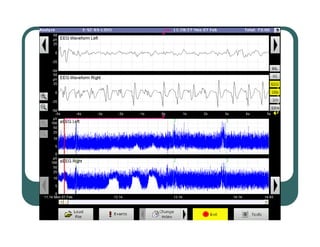

aEEG – How is it derived?

z Background + Transients

z Filtered, rectified

z Compressed - reams of paper in one screen

EEG

Courtesy T.

Courtesy T. Weiler

Weiler, Olympic Medical

, Olympic Medical

aEEG – Typical tracings

z CFM studies

have prognostic

significance post-

asphyxial injury

z Faster recovery

of CFM yields

better prognosis

at two years